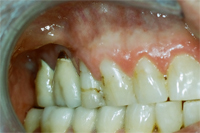

Ein 31 Jahre alter Patient zeigt einen starke Zahnfleisch-Rückgang im Oberkiefer (Abb. 1 und 3) und wir beschliessen, diese Rezessionen zu behandeln.

Der Erfolg der Behandlung ist deutlich in den Abb. 2 und 4 zu sehen. Sehr augenfällig konnte die Situation um den Eckzahn im linken Oberkiefer verbessert werden (vergleiche dazu Abb. 3 vorher und Abb. 4 nachher).